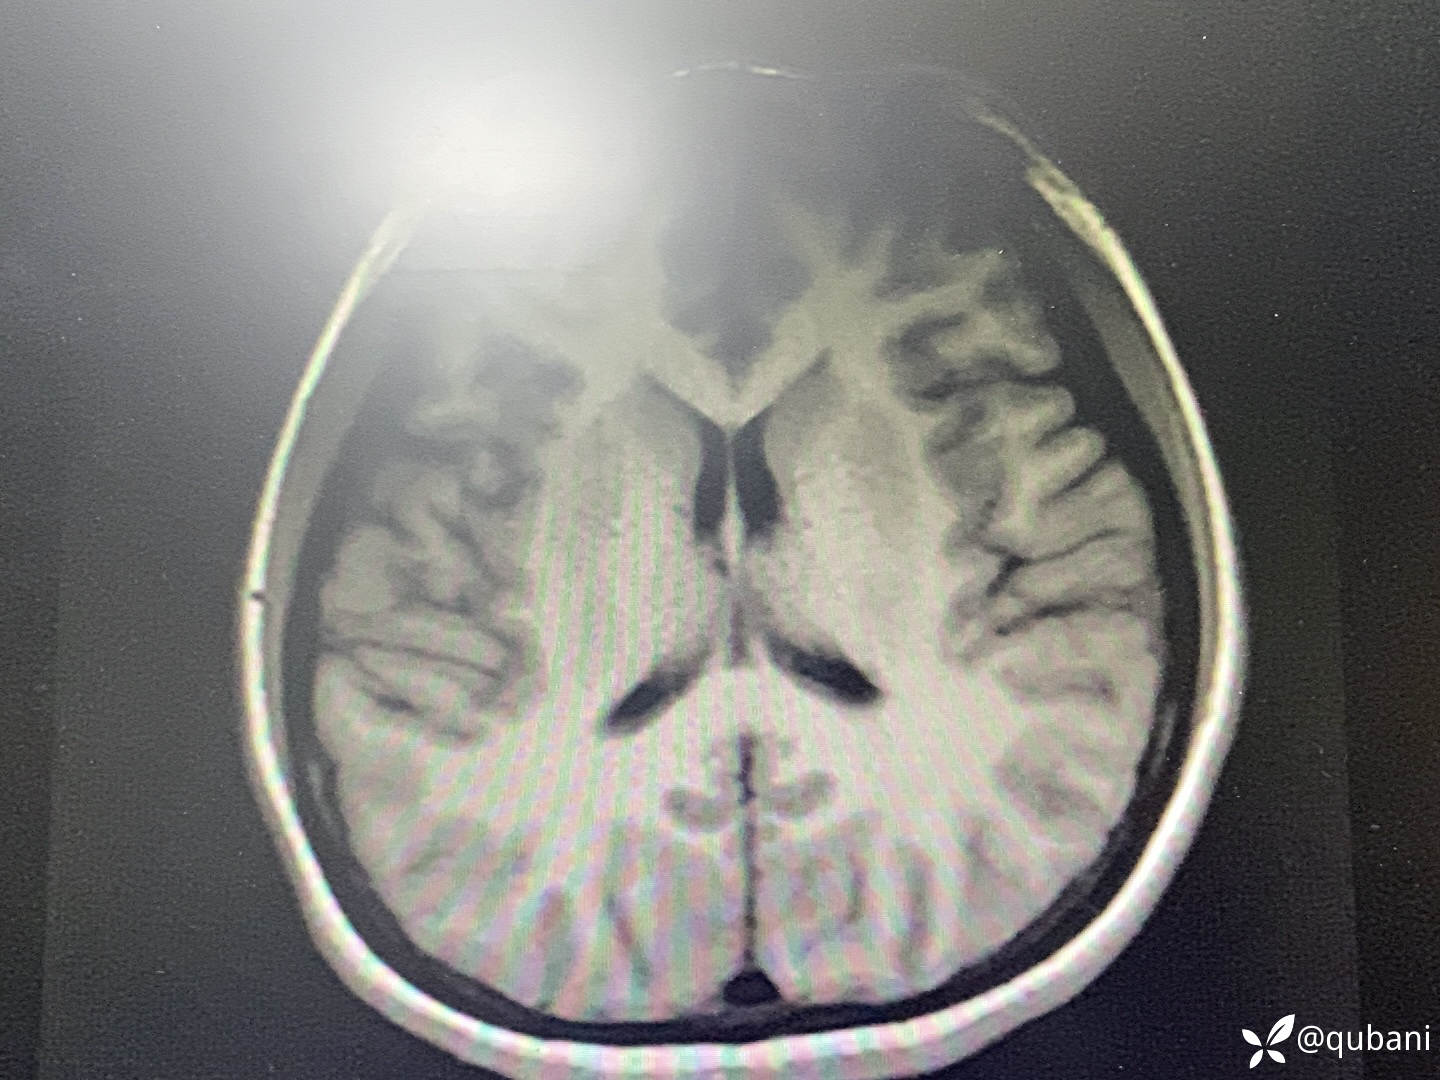

头MRI+DWI